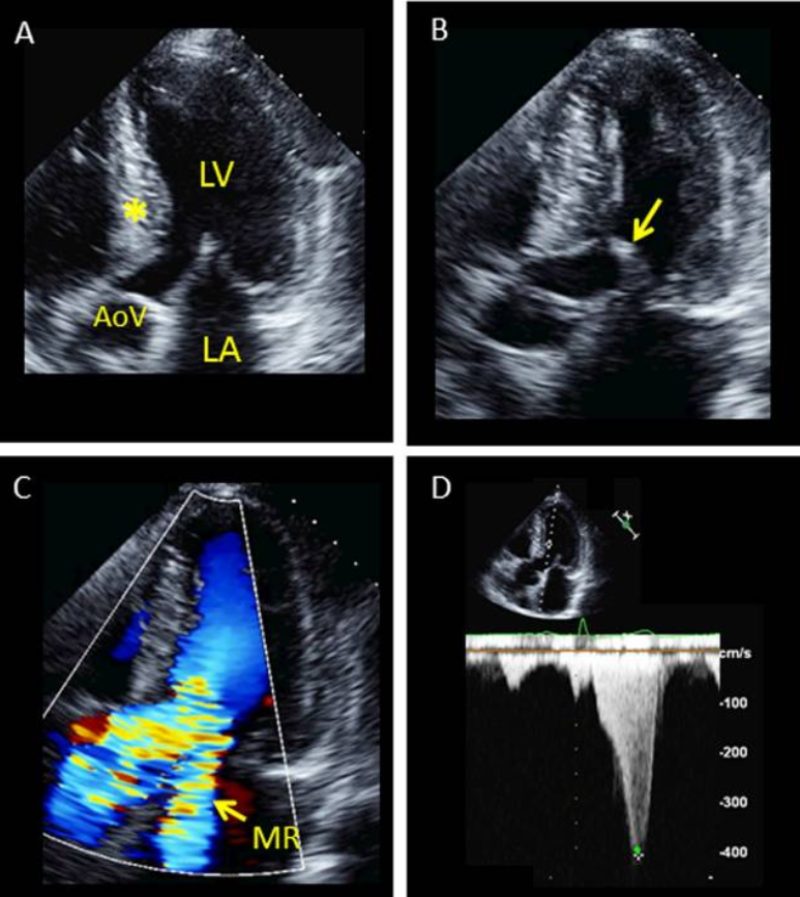

Hình ảnh siêu âm là một dữ liệu quan trọng trong việc chẩn đoán bệnh cơ tim phì đại và nhiều vấn đề tim mạch khác. Dưới đây là một số hình ảnh siêu âm thực tế.